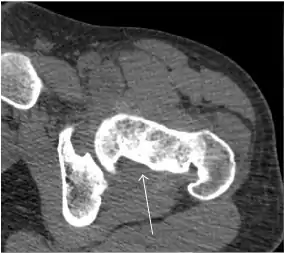

Computed Tomography

Due to radiation concerns, CT has been relegated after MRI in the study of intra-articular causes of hip pain. The only exception where CT is considered superior to MRI is in bone tumors, because of its ability in characterizing matrix calcifications, and in depicting the anatomy of acute traumatic fractures. Typical matrix calcifications include the following: (a) osteoid mineralization, like a dense cloud, (b) chondroid calcification, reproducing a punctate popcorn pattern, or (c) fibrous calcification, ground glass-like appearance. There are also tumors that typically do not show matrix calcification. CT is also used for accurate localization of the nidus in osteoid osteomas and this must be differentiated from Brodie’s abscess or a stress fracture. The current standard treatment of osteoid osteoma is percutaneous radiofrequency ablation and this is usually performed under CT guidance.[1]

Quite often, CT is widely available unlike MRI, especially in the acute setting. CT is performed in this setting when doubt about the existence of a fracture persists following plain radiograph. Modern multidetector computed tomography (MDCT) shows results comparable with MRI for detecting occult fractures.[1]